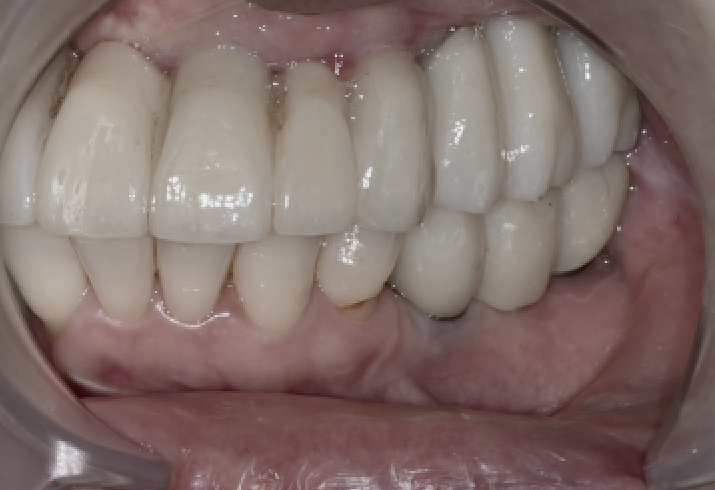

Stabilizing the bite with PMMA temporary prostheses

After implant treatment at Seoulove Dental Hospital

we used precision scanning to create upper and lower

full PMMA temporary prostheses.

When first fitted, speech or chewing sensations may feel unfamiliar,

but

we repeated bite adjustments, resin additions (Add), and height adjustments several times

until the patient found the most comfortable fit.

The patient said,

"It’s been a long time since I felt that biting with my front teeth again"

and

"I can feel the texture of food again,"

expressing satisfaction.